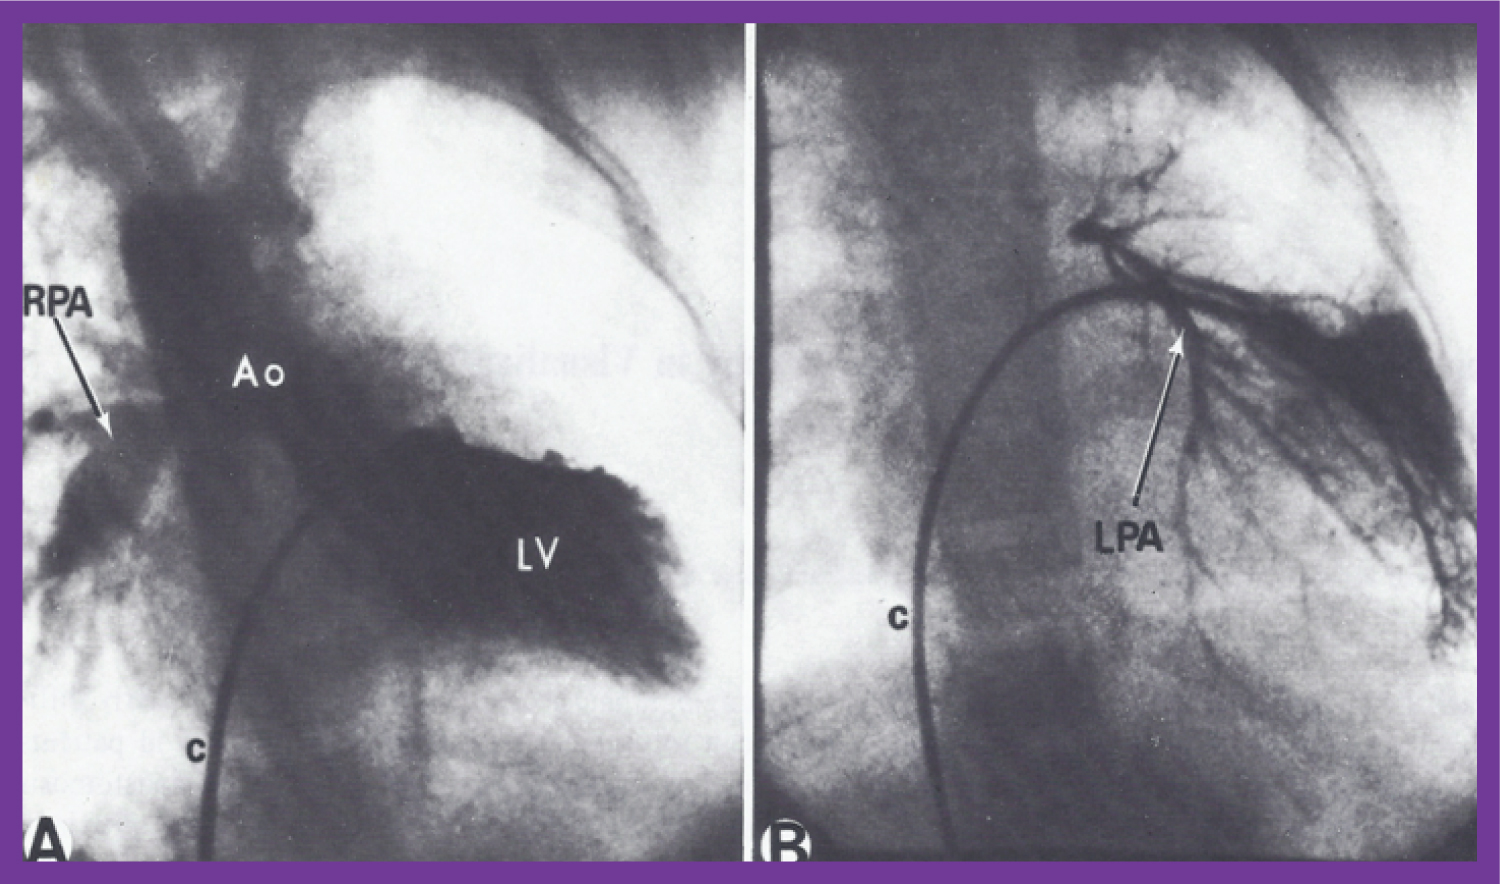

Figure 13: A) Selected frame of a left ventricular (LV) cineangiogram in postero-anterior view, demonstrating the opacification of the aorta (Ao) with a visualization of the right pulmonary artery (RPA) without the opacification of the left pulmonary artery (LPA). The catheter (c) is positioned in the LV via the patent foramen ovale and left atrium (not marked); B) Selected frame of a pulmonary venous wedge cineangiogram, clearly demonstrating the size of the LPA. The catheter is positioned in the pulmonary venous wedge position via the patent foramen ovale and left atrium (not marked) [62]. View Figure 13

The presentation also included manifestation of non-opacification of patent ductus arteriosus in patients with large proximal shunts [65], outcome of intra-arterial injection of heparin on the complications associated with percutaneous arterial catheterization [66], depiction of a new technique of left ventricular and aortic catheterization and angiography via a patent ductus arteriosus [67,68], value of balloon occlusion aortography in demonstrating proximal structures and aorto-pulmonary collateral vessels (Figure 15) [69], and documentation of aneurysms of the membranous ventricular septum resulting in pulmonary outflow tract obstruction in congenitally corrected transposition of the great arteries both in patients with levocardia (Figure 16) [52] and those with dextrocardia [53,54].